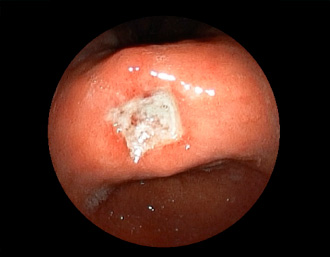

症例1:胃潰瘍(37才、男性)

①胃潰瘍(Stage A1)

健診:胃レントゲン検査で、胃角部ニッシェを指摘され当院受診。

胃角部小弯に、深くて大きな、大きさ約10mmの胃潰瘍(stage 1)

があり、潰瘍底は一部白苔はみ出しを認める。エソメプラゾールマグネシウム水和物投薬で治療開始しました。

(通常画像)